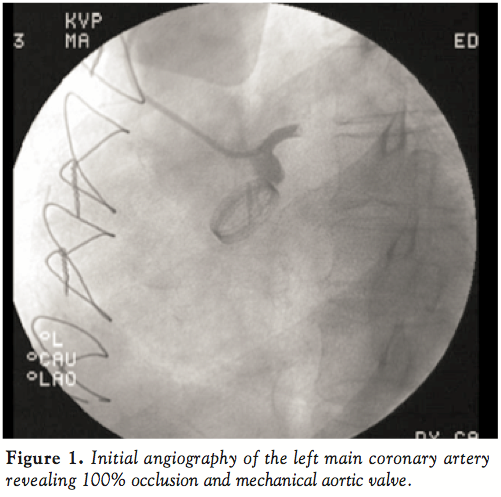

Diagnostic angiography of the left coronary system demonstrated complete occlusion of the LMCA (Figure 1). Fluoroscopy was also notable for a normal opening and closing bi-leaflet mechanical aortic valve. Given the scenario of cardiogenic shock, the decision was made to proceed with primary percutaneous coronary intervention. An intra-aortic balloon pump was placed for hemodynamic support. Intraveneous heparin and eptifibatide were administered with a peak activated clotting time of 293 seconds. A 300 cm BMW wire (Abbott Vascular) was advanced across the LMCA and positioned in the left anterior descending artery. After confirmation of intra-luminal location, a 2.0 x 15-mm Maverick balloon (Boston Scientific) was used to perform initial angioplasty of the LMCA with restoration of TIMI 2 flow, but with significant residual thrombus burden. Next, a 6 Fr ExPort catheter (Medtronic) was used to perform aspiration thrombectomy without retrieval of visible thrombus. A 7 Fr ExPort catheter was subsequently used to perform additional thrombectomy passes with improvement in flow (Figure 2) and removal of visible clot (Figure 3). However, given a persistently large clot burden in the LMCA, the decision was made to stent the vessel and compress the thrombus against the vessel wall. The left circumflex was a small non-dominant vessel, and a 2.75 x 23-mm Vision bare-metal stent (Abbott Vascular) was deployed in the LMCA into the LAD. The stent was ultimately post-dilated with a 3.5 x 15-mm NC Quantum balloon (Boston Scientific) to high pressure. Final angiography revealed TIMI 3 flow and no significant disease in the LAD (Figure 4). The right coronary artery was similarly free of significant angiographic disease (Figure 5).